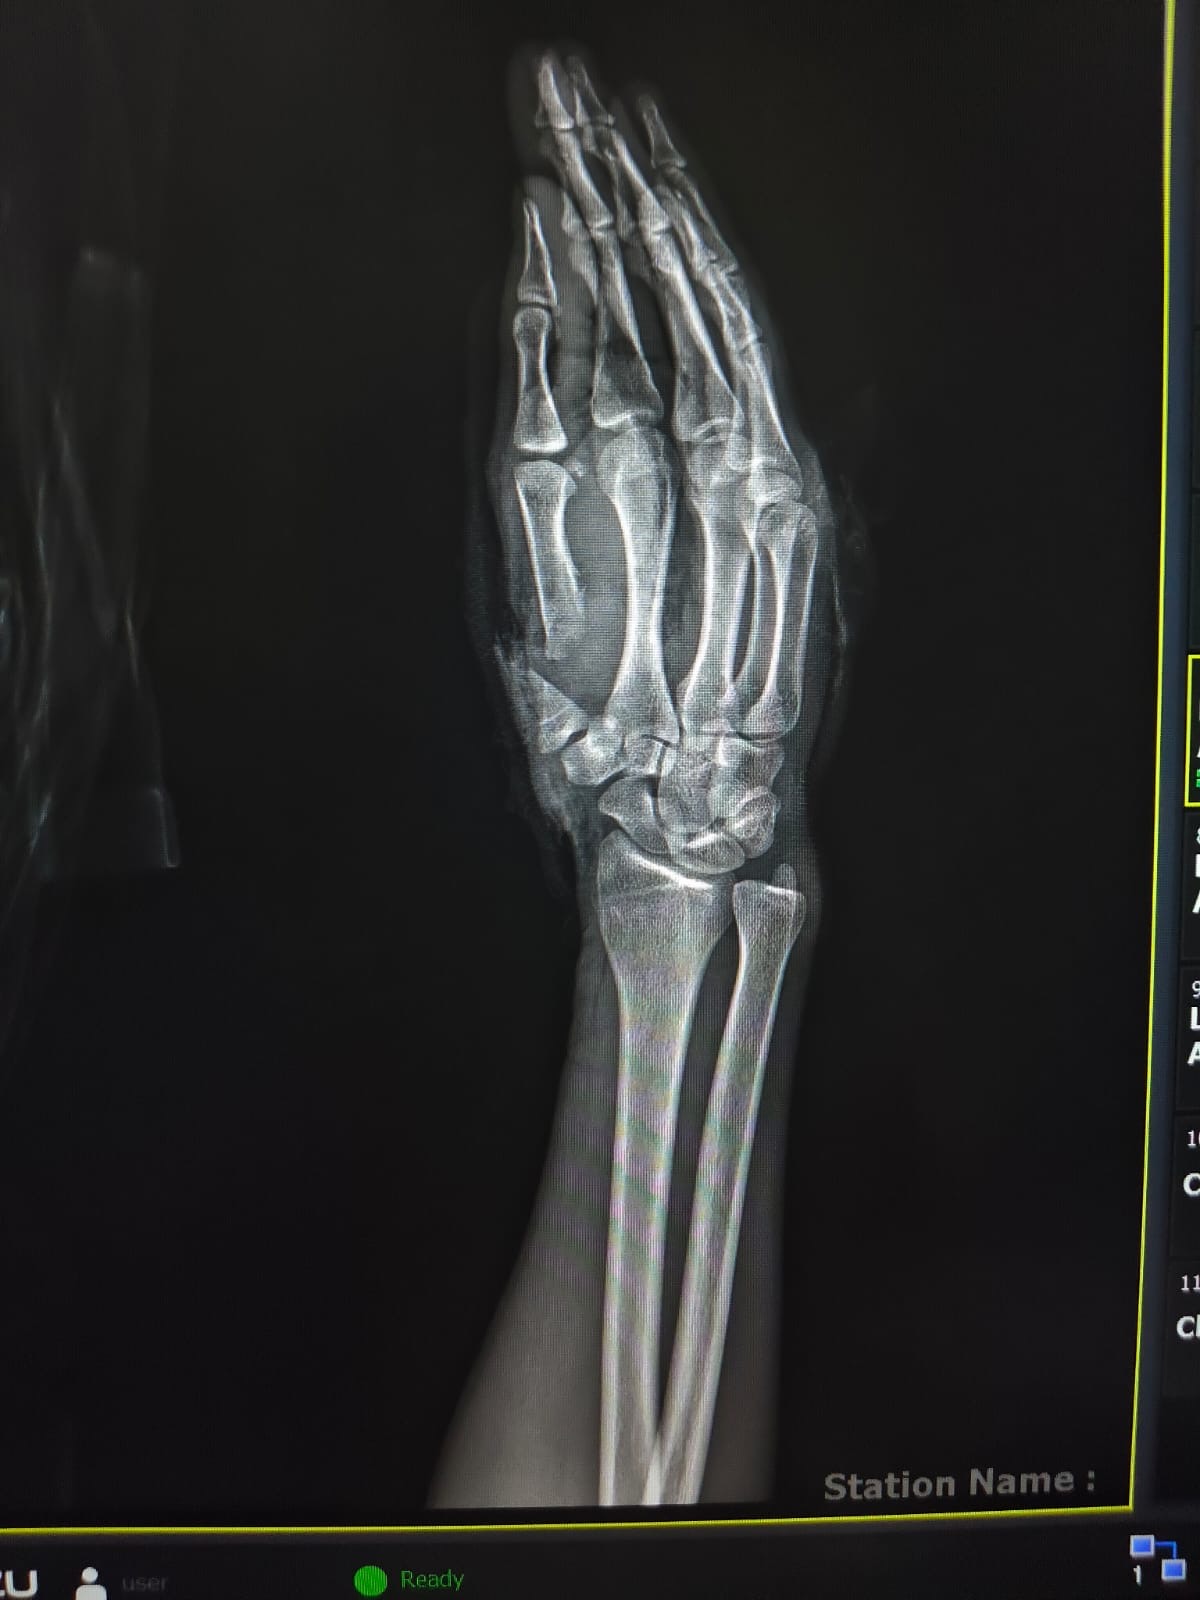

في جراحة 6 ساعات.. إنقاذ شاب تعرض لبتر كامل بإصبع الإبهام نتيجه ساطور بمستشفى سوهاج الجامعي

نجح فريق طبي بوحدة الجراحات الميكروسكوبية بمستشفى جامعة سوهاج في إنقاذ شاب يبلغ من العمر ٢٦ عامًا، مصابًا ببتر كامل في إصبع الإبهام لليد اليمنى، وقطع كامل بالشرايين والأوردة، إثر التعدي عليه بسلاح أبيض (ساطور).

ومن جانبه أوضح الدكتور مجدي القاضي عميد كلية الطب البشري جامعة سوهاج ورئيس مجلس إدارة المستشفيات الجامعية، أن الفريق الطبي نجح في إعادة زرع إصبع الإبهام باستخدام جراحة ميكروسكوبية دقيقة استغرقت نحو 6 ساعات، تم خلالها توصيل الشرايين والأوردة والأعصاب المغذية للإصبع، بالإضافة إلى تثبيت عظام الإصبع باستخدام أسلاك معدنية، مما ساهم في استعادة الدورة الدموية واستقرار الحالة.